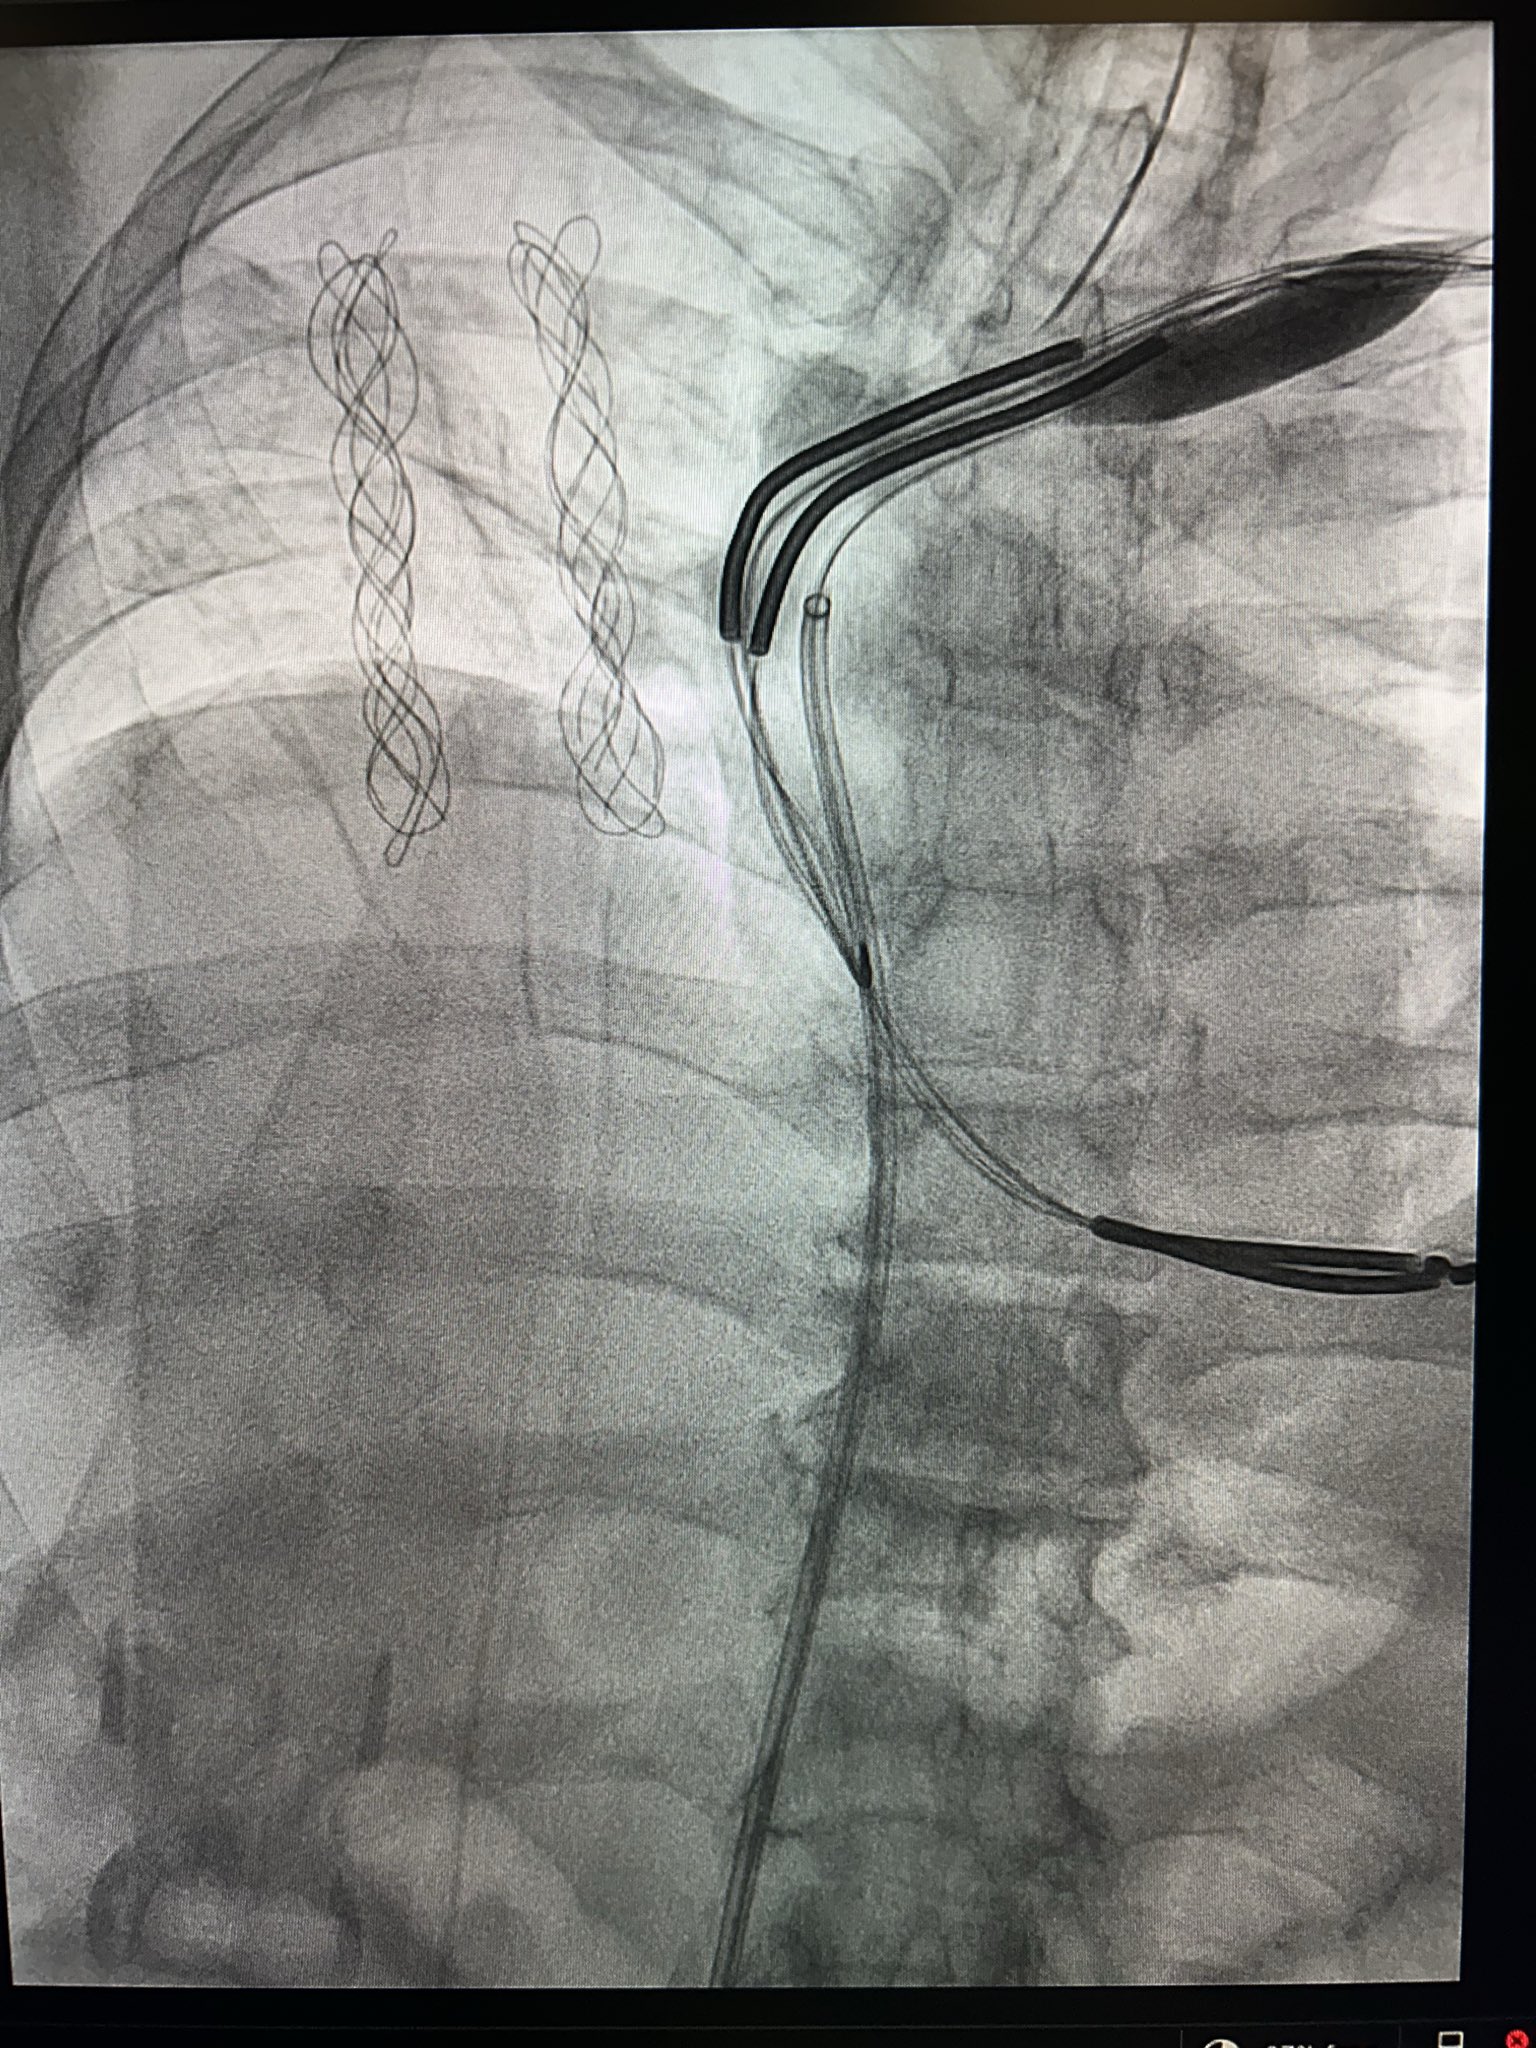

Patient with an abandoned 16 year old dual coil ICD lead, RA lead fracture, and generator at ERI.

Shockwave with a 12mm balloon to the axillary, subclavian, and SVC.

Extracted both leads with 16Fr laser and preserved existing ICD lead.

#Epeeps #extraction #shockwave